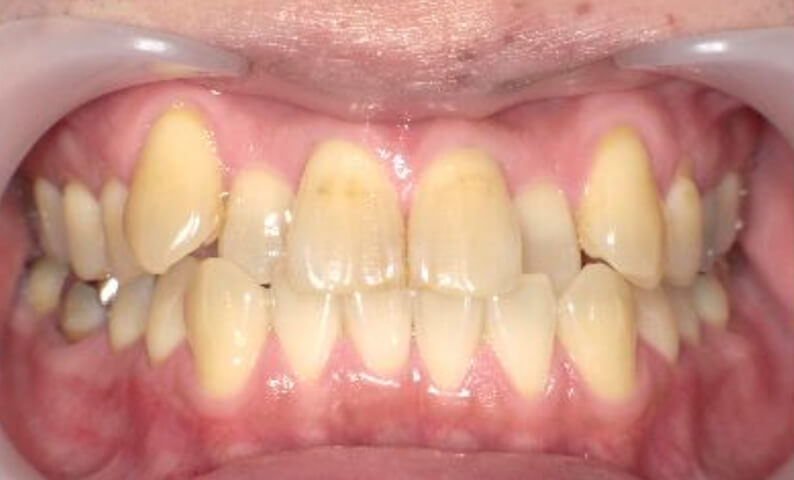

症例_003 上下顎の部分矯正

治療期間:12ヶ月金額:54万円+税男性八重歯前歯のガタガタ

| Before | After |